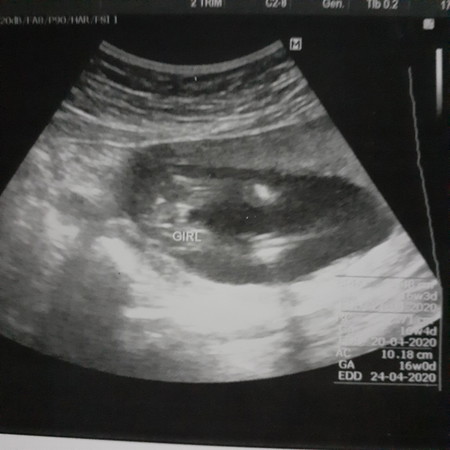

วันนี้หมอนัดตรวจซาวด์ดูปกติทุกอย่างหมอบอก16w6dสามรถดูเพศได้แล้วนะครับคุณเเม่เลยภาวนาในใจ ว่าอ้าให้หมอดูเลยนะลูกไม่ต้องอาย ใจแม่อยากได้ชาย เพราะมีลูกสาวแล้ว อิพ่ออยากได้ลูกสาวอิก ผลสรุป อ้าซ่าเลยจร้าหมอบอก3กลีบเลยคุณแม่ ปะได้ลูกสาวอิกก็ไม่เปนไรขอแค่เขาแข็งแรงก็พอ